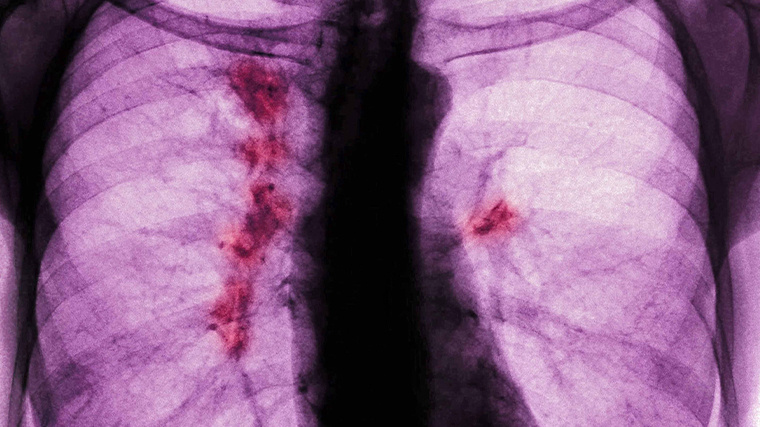

Рак легких — одно из самых распространенных и опасных онкологических заболеваний. Рак легких — одно из самых распространенных и опасных онкологических заболеваний в мире. Ежегодно оно уносит десятки тысяч жизней по всему миру, причем значительная часть случаев выявляется уже на поздних стадиях, когда шансы на успешное лечение резко снижаются. Несмотря на прогресс в диагностике и терапии, рак легких остается серьезной проблемой современной медицины. Рак легких — это злокачественное новообразование, которое развивается из клеток слизистой оболочки бронхов и легочных альвеол. Это одно из самых распространенных и смертоносных онкологических заболеваний в мире. В 2022 году в мире выявили около двух с половиной миллионов новых случаев рака легких, при этом около двух миллионов человек умерло от этого заболевания. В России ежегодно диагностируют примерно 50–60 тысяч новых случаев. Чаще всего заболевание развивается у людей старше 50 лет. Мужчины болеют в пять-семь раз чаще, чем женщины. Почти

В 2022 году в мире выявили около двух с половиной миллионов новых случаев рака легких, при этом около двух миллионов человек умерло от этого заболевания. В России ежегодно диагностируют примерно 50–60 тысяч новых случаев.

Чаще всего заболевание развивается у людей старше 50 лет. Мужчины болеют в пять-семь раз чаще, чем женщины. Почти каждая пятая смерть от злокачественных новообразований приходится на долю рака легких. В 70% случаев диагноз ставится на поздних стадиях, когда прогноз уже неблагоприятен.

В России рак легкого часто диагностируется на поздних стадиях: по некоторым оценкам, около 70–75% случаев выявляются на III–IV стадиях. В среднем в России выявляют около 59 тысяч новых случаев рака легкого в год.